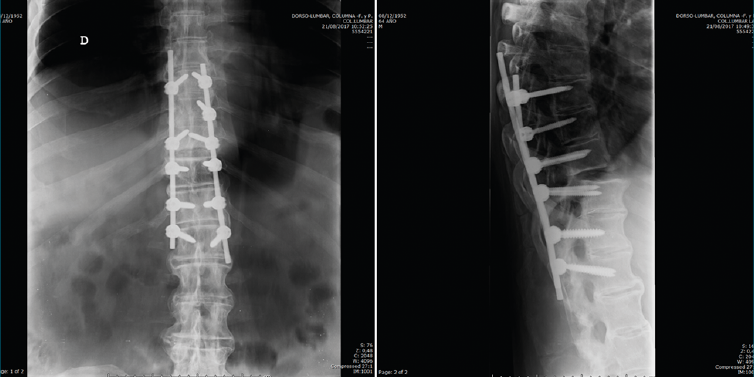

Se puede observar con más claridad la lesión traumática T10/T11 y la sindesmofitosis de todo el raquis en el corte sagital de una tomografía axial computarizada de cuerpo (body TAC) (Figura 2).

Figura 2. Corte sagital de tomografía axial computarizada dorsolumbar.

Figura 6. Control postoperatorio.

Después de realizar un control radiológico postoperatorio (Figura 6), inició la deambulación con ortesis semirrígida dorsolumbar en el postoperatorio inmediato. Mantuvimos la ortesis durante 2 meses, iniciando la rehabilitación con una evolución clínica excelente.

Figura 7. Control a los 2 meses de la cirugía.

Se realizó un control a los 2 meses de la cirugía, previo al inicio de rehabilitación (Figura 7).